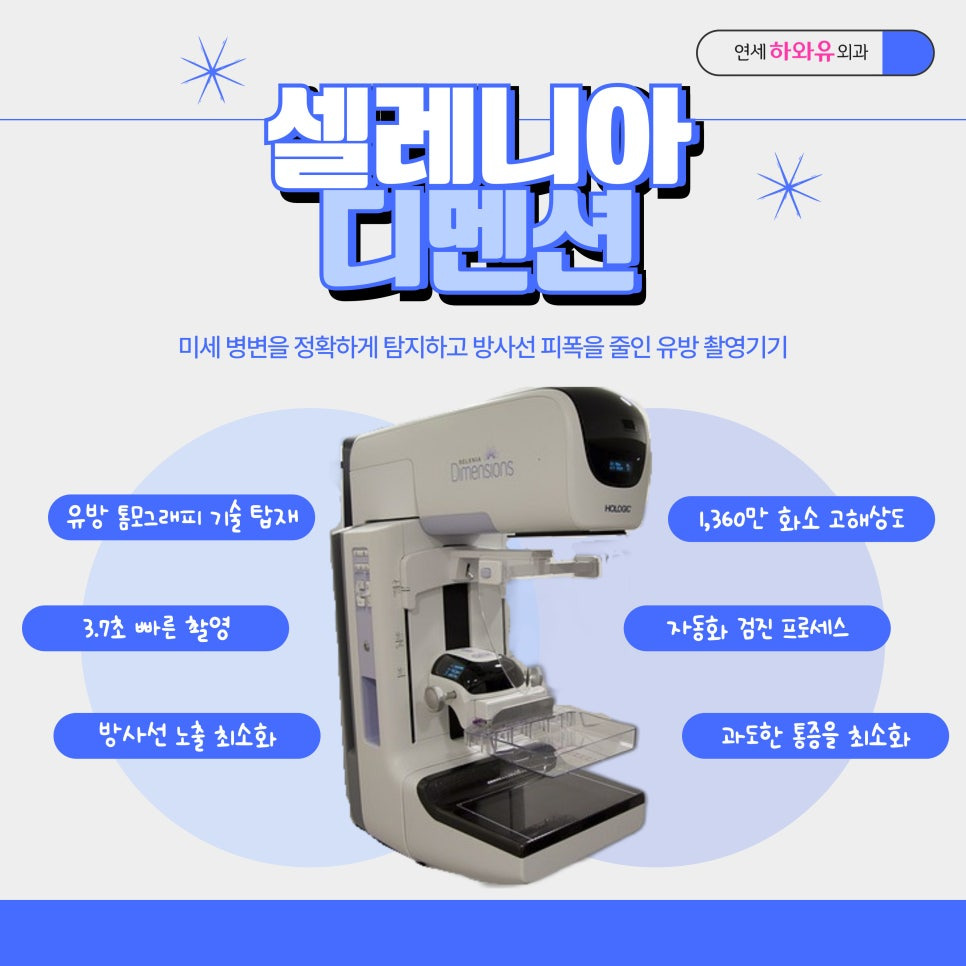

유방암 검진, 3D 유방촬영기 셀레니아디멘션 도입

하남유방외과 연세하와유외과에서는 환자분들의 유방을 정확하게 진단하기 위하여 3D 유방촬영기 셀레니아디멘션으로 유방검진을 도와드리고 있는데요. 이 장비는 유방을 얇은 단면으로 나누어 하나하나 정밀하게 촬영한 후, 1,360만 화소의 고해상도 3D 이미지로 구조화하여 병변을 더 잘 찾아낼 수 있도록 해줍니다.

① 인체공학적 곡선 커브로 제작되어 기존 기계보다 통증을 줄여줌

② 기존 촬영 대비 방사선 피폭량이 최대 50% 감소

③ 3.7초 내외의 빠른 촬영

④ 자동화된 시스템으로 정확한 검진이 가능

실제로 3D 유방촬영기 셀레니아디멘션 도입한 뒤, 유방암 진단하는데 정확도가 높아졌다고 알려졌는데요. 유방암 진단율이 약 41% 증가하고, 재촬영률도 40% 가까이 감소했다는 보고도 있습니다. 이 장비가 모든 병변을 발견할 수 있는 것은 아니지만, 정밀도 면에서는 기존 장비보다 한층 발전되었다는 평가를 받고 있습니다.

하남유방외과 연세하와유외과에서는 여성분들이 편안하게 검진을 받을 수 있도록 3D 유방촬영기 셀레니아디멘션 장비로 기존 유방촬영기계보다 덜 아프게 검진해 드리고 있는데요. 이상소견이 보일 때에는 맘모톰으로 당일 조직검사도 가능할 수 있도록 진료체계를 마련하고 있습니다.